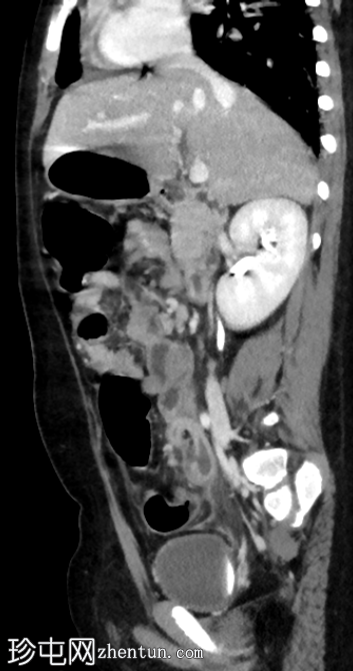

冠状位增强扫描(门静脉期)

阑尾扩张,壁增厚并强化,周围阑尾周围脂肪组织条索状改变。

阑尾尖端近端可见局灶性壁缺损。

该缺损旁可见一小环状强化积液。

结肠周围及肠系膜区可见多个肿大淋巴结。

腹膜增厚。

影像

学表现符合急性阑尾穿孔的诊断,阑尾尖端近端可见局灶性壁缺损。环状强化积液提示阑尾周围脓肿。

术中发现证实了影像诊断,阑尾发炎,阑尾尖端近端有壁缺损,阑尾周围区域有脓液积聚。